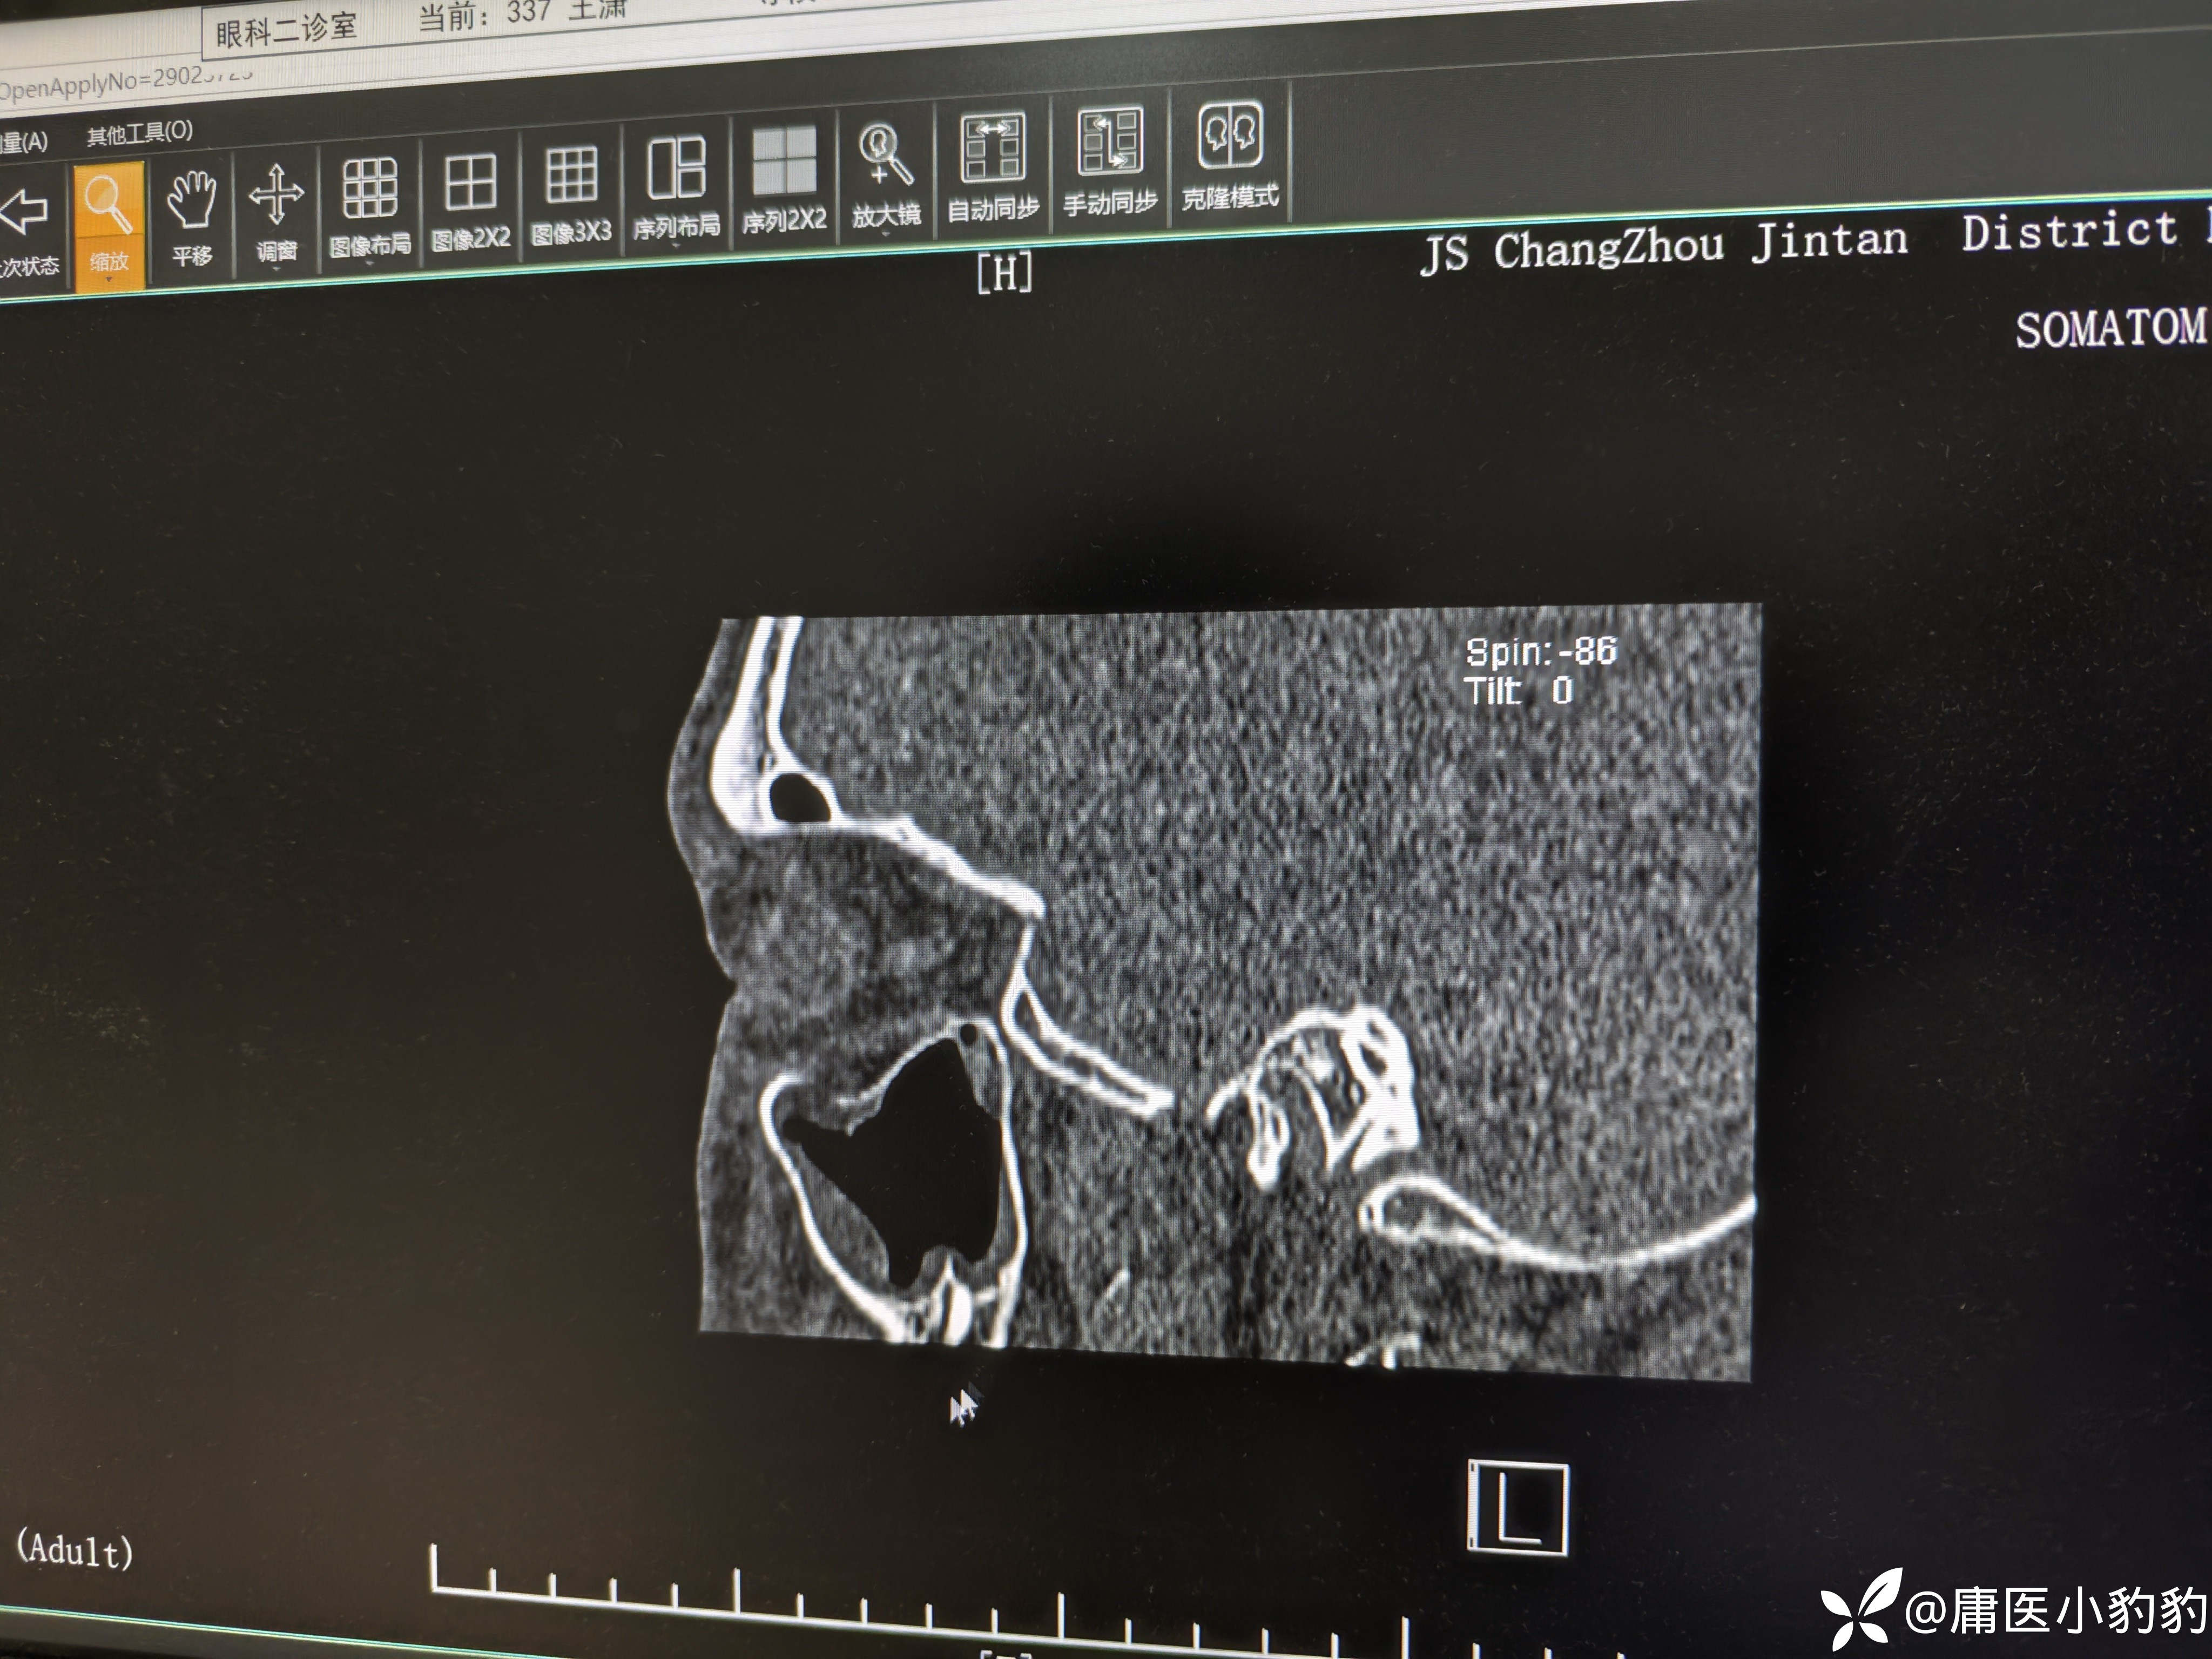

患者,男,26岁,五天前右面部外伤,右眼结膜下出血,主诉右眼视物模糊。眼眶CT示右上颌窦上壁骨折,右上颌窦内积血。眼科学检查示 矫正视力:右8.0/左1.0,眼压右18/左20,右眼视网膜震荡。无明显复视,重影,眼球运动未见明显受限,未行眼球牵拉试验。目前正在甘露醇+激素治疗观察。请问各位眼科的同门对该患者后续的治疗方案有何建议?